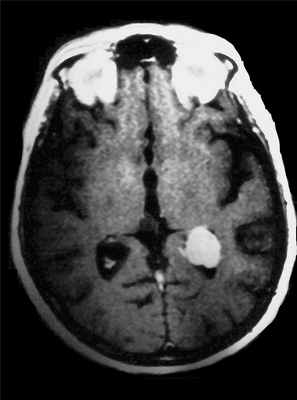

МРТ головного мозга. Менингиома серпа. Аксиальная и корональная Т1-взвешенные МРТ с контрастированием.

При МРТ головного мозга выявляется образование с широким основанием. Гиперостоз, часто видимый при КТ и на рентгенограммах, при МРТ головного мозга выглядит как утолщение внутренней костной пластинки свода черепа. Кальцинаты, обнаруживаемые при КТ в 20% наблюдений, при МРТ не видны. Опухоль при МРТ довольно однородная по структуре. Прорастание костей свода черепа видно отчетливо как участок повышенного сигнала на МРТ головного мозга любого типа в резко гипоинтенсивной кости. Сигнал от опухолевого узла на Т2-зависимых МРТ зависит от гистологического подтипа: относительно низкой интенсивности (между белым и серым веществом) при фибробластном и высокой при ангиобластном и синтициальном. Отек выражен в различной степени в каждом конкретном случае. Ряд МРТ признаков очень характерен для менингиомы: полоса ликвора между опухолью и тканью мозга, смещение окружающих сосудов. Они отражают неинвазивный характер роста. Смещенную и вовлеченную твердую мозговую оболочку иногда удается визуализировать при МРТ после введения гадолиния, особенно на корональных МРТ срезах. Усиление сигнала при МРТ с контрастированием от оболочки над опухолью с распространением в стороны (симптом “хвоста”) не абсолютно специфично и встречается при МРТ как при менингиоме, так и при лептоменингиальных метастазах. Однако при глиальных опухолях и невриноме при МРТ оно не описано. При обследовании пациентов методом МРТ в СПб с менингиомами серпа (фалькс-менингиомы) и намёта мозжечка рекомендуется делать МР-венографию для определения компрессии синуса и его проходимости. В наших центрах это обязательное исследование перед операцией. На открытом МРТ венография также легко выполнима. Не все центры МРТ СПб придерживаются этой методики.